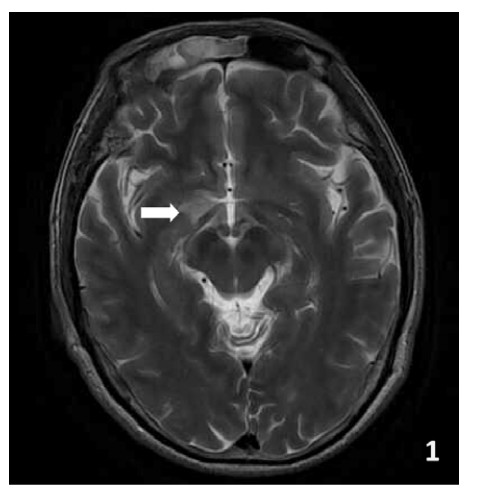

患者入院后体温偏高,查体见明显咽红、巩膜充血以及鼻塞流涕等上呼吸道症状,完善新型冠状病毒核酸检测呈阳性(Ct值:33.09),考虑合并新型冠状病毒感染,予以先诺特韦片0.75 g+利托那韦片0.1 g, 每12 h口服1次,连续服用5 d抗病毒治疗,抗病毒第4天起体温峰值下降,第6天起体温完全正常。住院早期患者胡言乱语、拔针、紧握床栏、躁动症状明显,并存在视幻觉,看见亲人在楼下并想要跳下去。邀请临床心理科会诊行精神检查:时间地点定向力不全,对答不切题,意志活动部分增强,躁动明显,自知力无。会诊考虑患者谵妄状态,予以奥氮平7.5 mg每晚睡前1次、丙戊酸钠缓释片500 mg每晚睡前1次对症治疗,并建议积极排查相关器质性疾病。住院期间复查头颅MRI检查(见图 1)提示右侧颞极异常信号灶。根据患者急性起病,以发热、意识障碍、精神异常为主要症状以及体格检查,检验检查结果,排除了中毒性脑病、肺性脑病、胰性脑病,糖尿病酮症酸中毒、甲亢危象等内科疾病,定位在中枢神经系统,根据神经系统疾病定性诊断的“Midnighs”原则:M(metablism, 代谢性)、I(inflammation,炎症)、D(degeneration,变性)、N(neoplasm,肿瘤)、I(infection,感染)、G(gland,腺体内分泌)、H(hereditary,遗传)、T(toxication,中毒/trauma,外伤)、S(stroke,卒中),考虑到患者中年起病,起病急,外貌体型发育无殊,无明显既往病史及家族史,起病前无明显外伤、有毒有害物质接触史,影像学检查不符合脑血管疾病或占位性病变,最终优先考虑炎症性及感染性相关病因。结合病史、症状及腰椎穿刺脑脊液等相关辅助检查结果,颅内急性感染性依据欠充分,考虑患者抗GlyR1抗体脑炎。与患方沟通病情,建议予激素及丙种球蛋白针使用,患方因家庭经济原因难以承担丙种球蛋白针费用,考虑到患者存在副鼻窦的慢性真菌感染,甲泼尼龙针未用到1 000 mg/d,予500 mg冲击治疗,同时辅以护胃、抗新冠病毒等治疗。连用4 d减甲泼尼龙针为240 mg 1次/d,2 d后减为60 mg 1次/d,2周后,改口服泼尼松片60 mg/d,此后每2周减5 mg(见图 3)。患者在使用激素3 d后体温正常,在使用激素8 d后精神行为异常症状明显改善,神志清楚,与人交流增多,对答大部分切题,睡眠昼夜节律恢复,病程中无痫样发作情况。随访至今,患者于家中休养并口服泼尼松片维持,日常生活实现自理。

T2轴位见右侧颞极异常高信号灶(箭头) 图 1 患者头部磁共振成像

在此,笔者报告一例新型冠状病毒感染同时合并抗GlyR1抗体阳性的AE患者。患者以非特异性神经症状起病,MRI示右侧颞叶异常信号灶,抗神经细胞抗体检测提示抗GlyR1抗体阳性,临床诊断为抗GlyR1抗体阳性AE,其接受了早期抗病毒治疗、激素冲击及后续口服续贯治疗,目前随访症状稳定,少见发作。